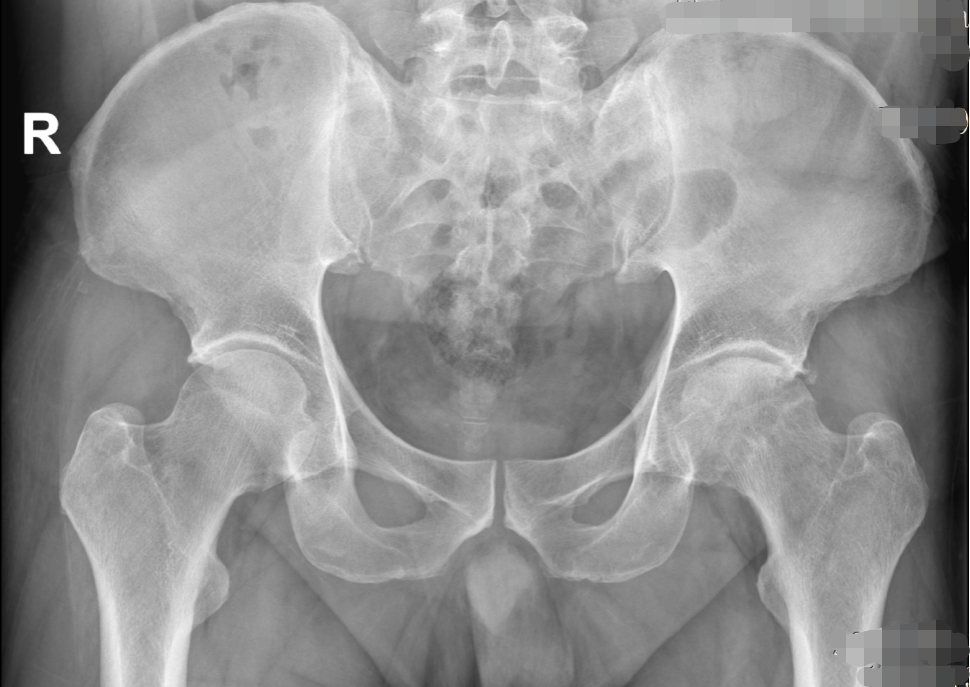

近日,我院骨科在南方医科大学第三附属医院(以下简称“南医三院”)派驻专家、学科带头人胡舒主任的带领下,为一名43岁的壮年患者吴先生(化名)实施左侧全髋关节置换术。

吴先生长期遭受左侧髋关节疼痛、活动受限,行走甚至休息时都很痛苦,已经严重影响工作和日常生活。

经胡舒主任详细检查,吴先生确诊为左侧股骨头缺血性坏死(三期)。由于保守治疗效果不佳,为有效改善功能、缓解症状,胡舒主任建议进行全髋关节置换。在充分沟通和了解了自己的疾病及治疗方式后,吴先生选择在家门口的东凤人民医院手术治疗,方便了家人护理和后续自己的定期复诊。

术前(骨盆正位)                                                                                                                           术后(骨盆正位)